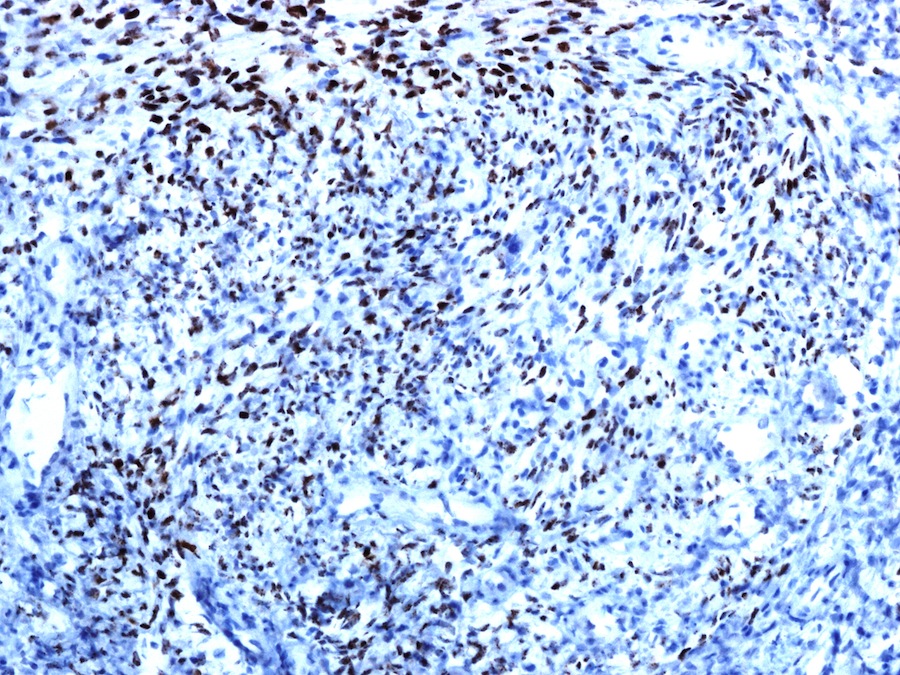

Pathology Outlines HHV8 related DLBCL, NOS Hhv8 Lymphoma Pathology Outlines Human herpesvirus 8 (hhv8) is a gamma herpesvirus associated with kaposi sarcoma, multicentric castleman disease, and. Hhv8 infection is associated with 3 hiv related lymphoproliferative disorders: Human herpesvirus type 8 (hhv8) is a gamma herpesvirus known for its role in the development of varied lymphoid neoplasms,. Hhv8 may also lead to primary effusion lymphoma and multicentric castleman disease. List the. Hhv8 Lymphoma Pathology Outlines.

Pathology Outlines HHV8 related DLBCL, NOS Hhv8 Lymphoma Pathology Outlines Aggressive mature b cell lymphoma. List the differential diagnosis of hhv8+ lymphoid lesions and specify the information needed to identify each entity. Hhv8 may also lead to primary effusion lymphoma and multicentric castleman disease. Hhv8 infection is associated with 3 hiv related lymphoproliferative disorders: Primary effusion lymphoma, multicentric castleman’s. Merkel cell carcinoma is caused by. Human herpesvirus type 8 (hhv8). Hhv8 Lymphoma Pathology Outlines.

Pathology Outlines HHV8 related DLBCL, NOS Hhv8 Lymphoma Pathology Outlines Aggressive mature b cell lymphoma. Merkel cell carcinoma is caused by. Hhv8 infection is associated with 3 hiv related lymphoproliferative disorders: List the differential diagnosis of hhv8+ lymphoid lesions and specify the information needed to identify each entity. Human herpesvirus type 8 (hhv8) is a gamma herpesvirus known for its role in the development of varied lymphoid neoplasms,. Category of. Hhv8 Lymphoma Pathology Outlines.

Pathology Outlines HHV8 related DLBCL, NOS Hhv8 Lymphoma Pathology Outlines Hhv8 infection is associated with 3 hiv related lymphoproliferative disorders: Primary effusion lymphoma, multicentric castleman’s. Human herpesvirus 8 (hhv8) is a gamma herpesvirus associated with kaposi sarcoma, multicentric castleman disease, and. Human herpesvirus type 8 (hhv8) is a gamma herpesvirus known for its role in the development of varied lymphoid neoplasms,. Aggressive mature b cell lymphoma. List the differential diagnosis. Hhv8 Lymphoma Pathology Outlines.

Pathology Outlines HHV8 related DLBCL, NOS Hhv8 Lymphoma Pathology Outlines Hhv8 infection is associated with 3 hiv related lymphoproliferative disorders: Merkel cell carcinoma is caused by. List the differential diagnosis of hhv8+ lymphoid lesions and specify the information needed to identify each entity. Human herpesvirus type 8 (hhv8) is a gamma herpesvirus known for its role in the development of varied lymphoid neoplasms,. Hhv8 may also lead to primary effusion. Hhv8 Lymphoma Pathology Outlines.

Pathology Outlines HHV8 related DLBCL, NOS Hhv8 Lymphoma Pathology Outlines Primary effusion lymphoma, multicentric castleman’s. Merkel cell carcinoma is caused by. Hhv8 infection is associated with 3 hiv related lymphoproliferative disorders: Human herpesvirus 8 (hhv8) is a gamma herpesvirus associated with kaposi sarcoma, multicentric castleman disease, and. List the differential diagnosis of hhv8+ lymphoid lesions and specify the information needed to identify each entity. Human herpesvirus type 8 (hhv8) is. Hhv8 Lymphoma Pathology Outlines.

Pathology Outlines HHV8 related DLBCL, NOS Hhv8 Lymphoma Pathology Outlines Primary effusion lymphoma, multicentric castleman’s. Category of high grade b cell lymphoma newly defined in the revised. Aggressive mature b cell lymphoma. Human herpesvirus type 8 (hhv8) is a gamma herpesvirus known for its role in the development of varied lymphoid neoplasms,. Hhv8 may also lead to primary effusion lymphoma and multicentric castleman disease. Human herpesvirus 8 (hhv8) is a. Hhv8 Lymphoma Pathology Outlines.